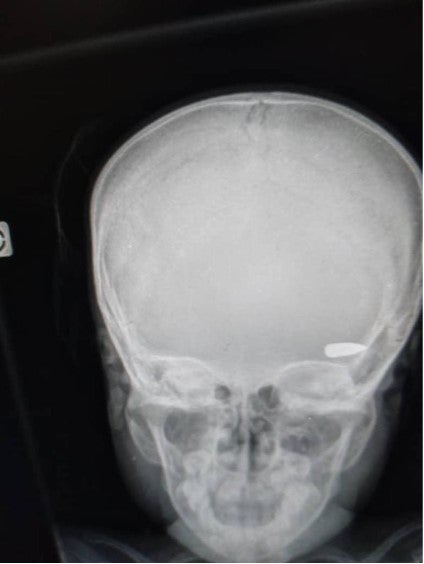

Una radiografía muestra una bala alojada en la cabeza de un niño que fue impactado durante un enfrentamiento entre grupos criminales en el barrio Brooklyn de la comuna de Cité Soleil a principios de abril de 2023.

Una radiografía muestra una bala alojada en la cabeza de un niño que fue impactado durante un enfrentamiento entre grupos criminales en el barrio Brooklyn de la comuna de Cité Soleil a principios de abril de 2023.